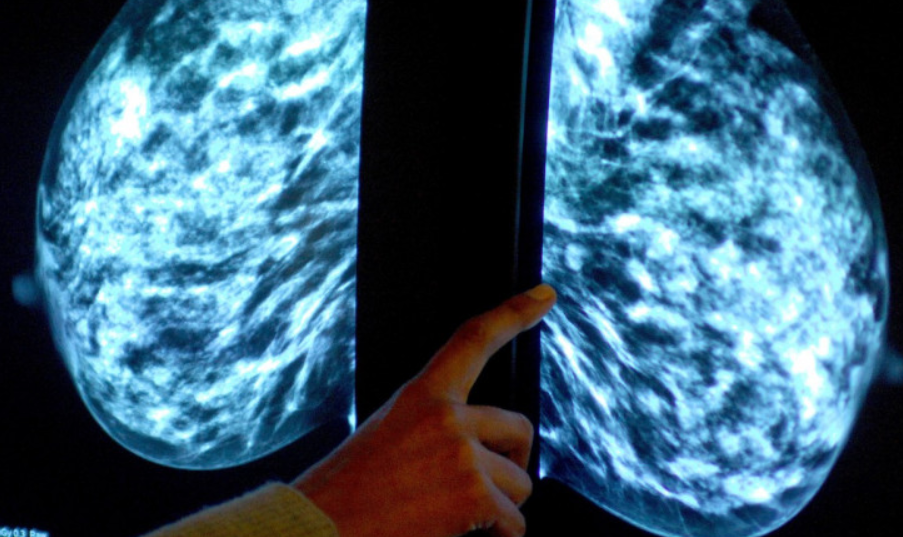

Aproximativ o sută de milioane de teste de rutină pentru cancer au fost anulate pe durata pandemiei, în Europa, ceea ce îi face pe experţii medicali să estimeze că în jur de un milion de cazuri au rămas nediagnosticate, se arată într-un raport al publicaţiei medicale The Lancet, citat de The Guardian și digi24.ro.

Mai mult, 50% dintre pacienţii care aveau cancer au fost nevoiţi să-şi amâne operaţiile sau şedinţele de chimioterapie, se mai arată în raport. "Estimăm că aproximativ un milion de cancere au rămas nediagnosticate în toată Europa în timpul pandemiei de COVID-19.

Suntem într-o cursă contracronometru pentru a depista aceste cazuri", a declarat profesorul Mark Lawler, de la Universitatea Belfast, preşedintele comisiei care a întocmit raportul. "În plus, a fost afectată serios şi cercetarea oncologică. Laboratoarele au fost închise, iar testele clinice au fost anulate în primul val al pandemiei. Suntem îngrijoraţi că Europa se îndreaptă către o epidemie de cancer în următorul deceniu, dacă cercetarea în privinţa cancerului nu va deveni o prioritate a sistemelor naţionale de sănătate", a adăugat acesta. Un alt efect al pandemiei este că pacienţii care se prezintă acum la medic au forme mai grave ale bolii.

"Există dovezi că o proporţie mai mare de pacienţi sunt diagnosticaţi cu cancere în stadii mai avansate în comparaţie cu perioada pre-pandemică, ca urmare a întârzierilor substanţiale când vine vorba de diagnosticare şi tratament. Acest lucru va pune presiune pe sistemele oncologice europene pentru mulţi ani de acum înainte", se arată în raport. Documentul mai arată că programele de prevenire sau depistare timpurie a cancerului nu primesc o finanţare adecvată în Europa.

"Se estimează că 40% dintre cazurile de cancer din Europa ar putea fi prevenite dacă programele de prevenţie ar folosi mai eficient datele pe care le avem despre factorii de risc care duc la apariţia bolii", a declarat Anna Schmütz, de la Agenţia Internaţională pentru Cercetarea Cancerului.